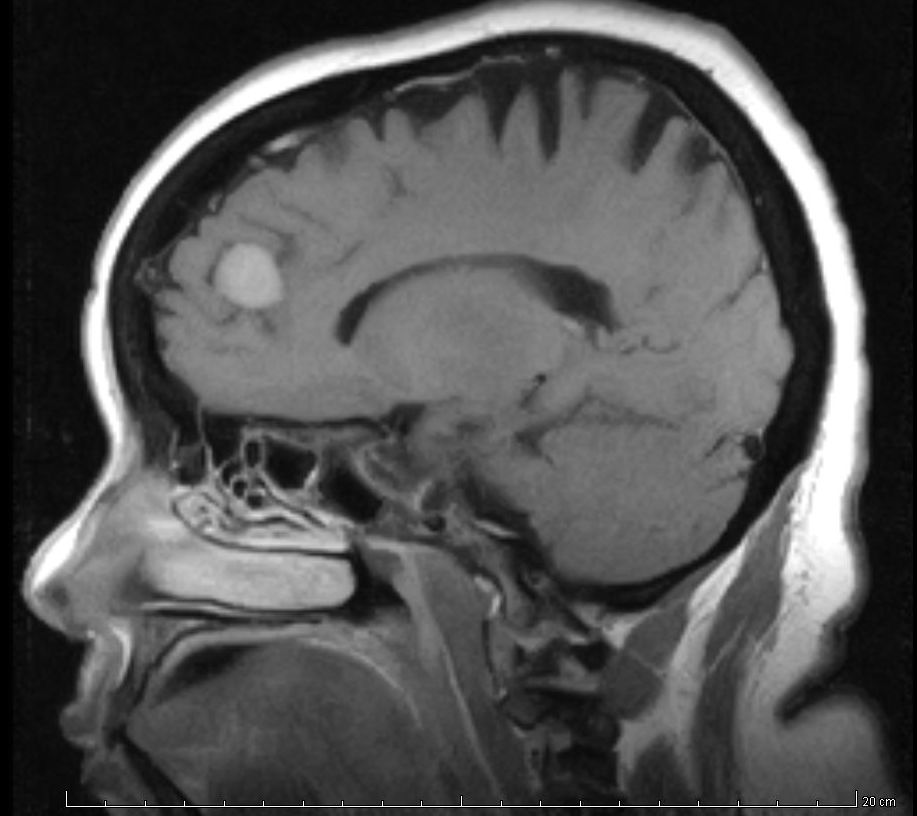

¿Cuántos pacientes con EPOC diagnosticada la tienen realmente?

Chest, 28 de agosto de 2019 Los diagnósticos de enfermedad pulmonar obstructiva crónica fueron incorrectos en aproximadamente el 62% de los casos.